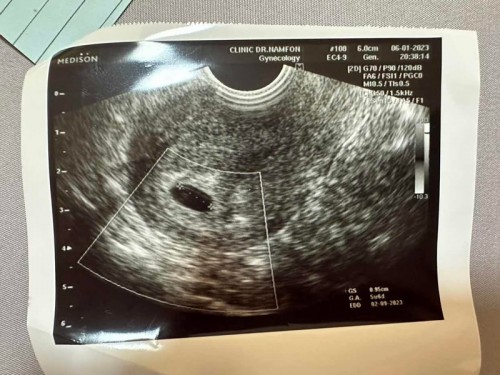

ขอดูใบซาวของแม่ แม่ 5-6 wk หน่อยค่า

ขอดูใบซาวของแม่ แม่ 5-6 wk หน่อยค่า เจอตัวน้อง กันหรือยังคะ บ้านนี้ไปซาวมาหมอบอก ยังไม่เจอตัวน้องเลย แอบกังวลค่ะ ท้องแรกท้องลม ไป กลัวเป็นเหมือนเดิมอีกค่ะมีแม่แม่คนไหนเคยท้องลมมาก่อนไหมคะ